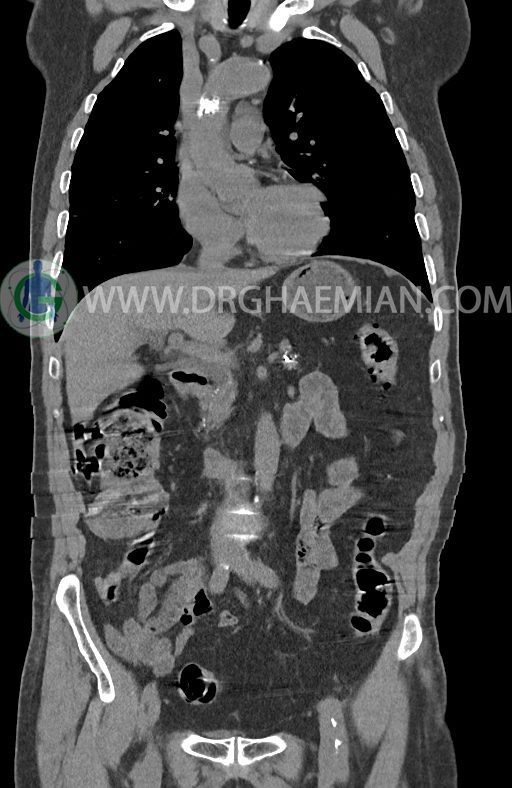

در سی تی اسکن اسپیرال ریه ها و مدیاستن، شکم و لگن با و بدون کنتراست وریدی (مولتی دیدکتور 16 با مقاطع ظریف و بازسازی کرونال) :

–افزایش ضخامت تومورال دیستال مری و GEJ در سگمانی به طول 4cm-5cm (T2 or T3)

-3 لنف نود رژیونال با SAD ≤ 9 mm دیده می شود. (N2)

–توده هیپودنس به قطر 10mm در پارانشیم طحال مشهود است. Quadriphasic MRI پیشنهاد می گردد.

–آتروفی نسبی پانکراس همراه با فوکوس های کلسیفیه ی منتشر پارانشیم مطرح کننده ی پانکراتیت مزمن

-CBD بسیار دیلاته (16mm) همراه با دیلاتاسیون مجاری داخل کبدی سنترال بدون شواهد سنگ یا توده در مسیر

–کیست های کورتیکال متعدد هر دو کلیه به بزرگترین قطر 56mm

–پروستات به دیامتر عرضی بزرگ حاوی فوکوس کلسیفیه

نتیجه : T(2or3)/N2/M0